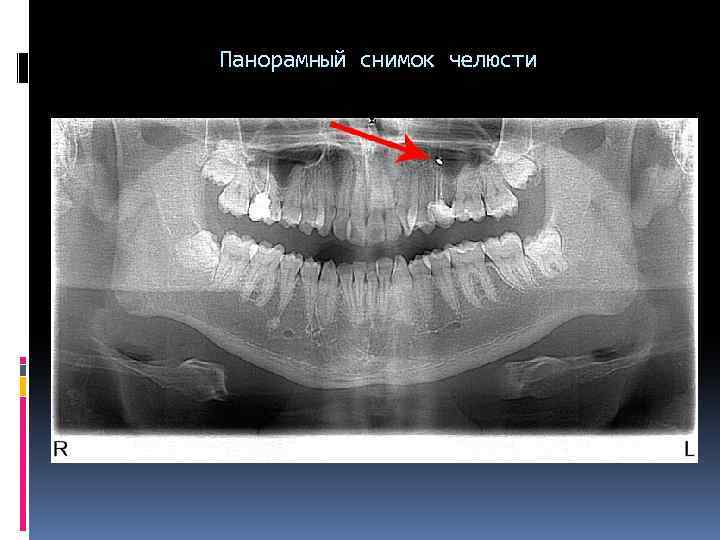

Панорамный снимок челюсти Панорамный снимок челюсти